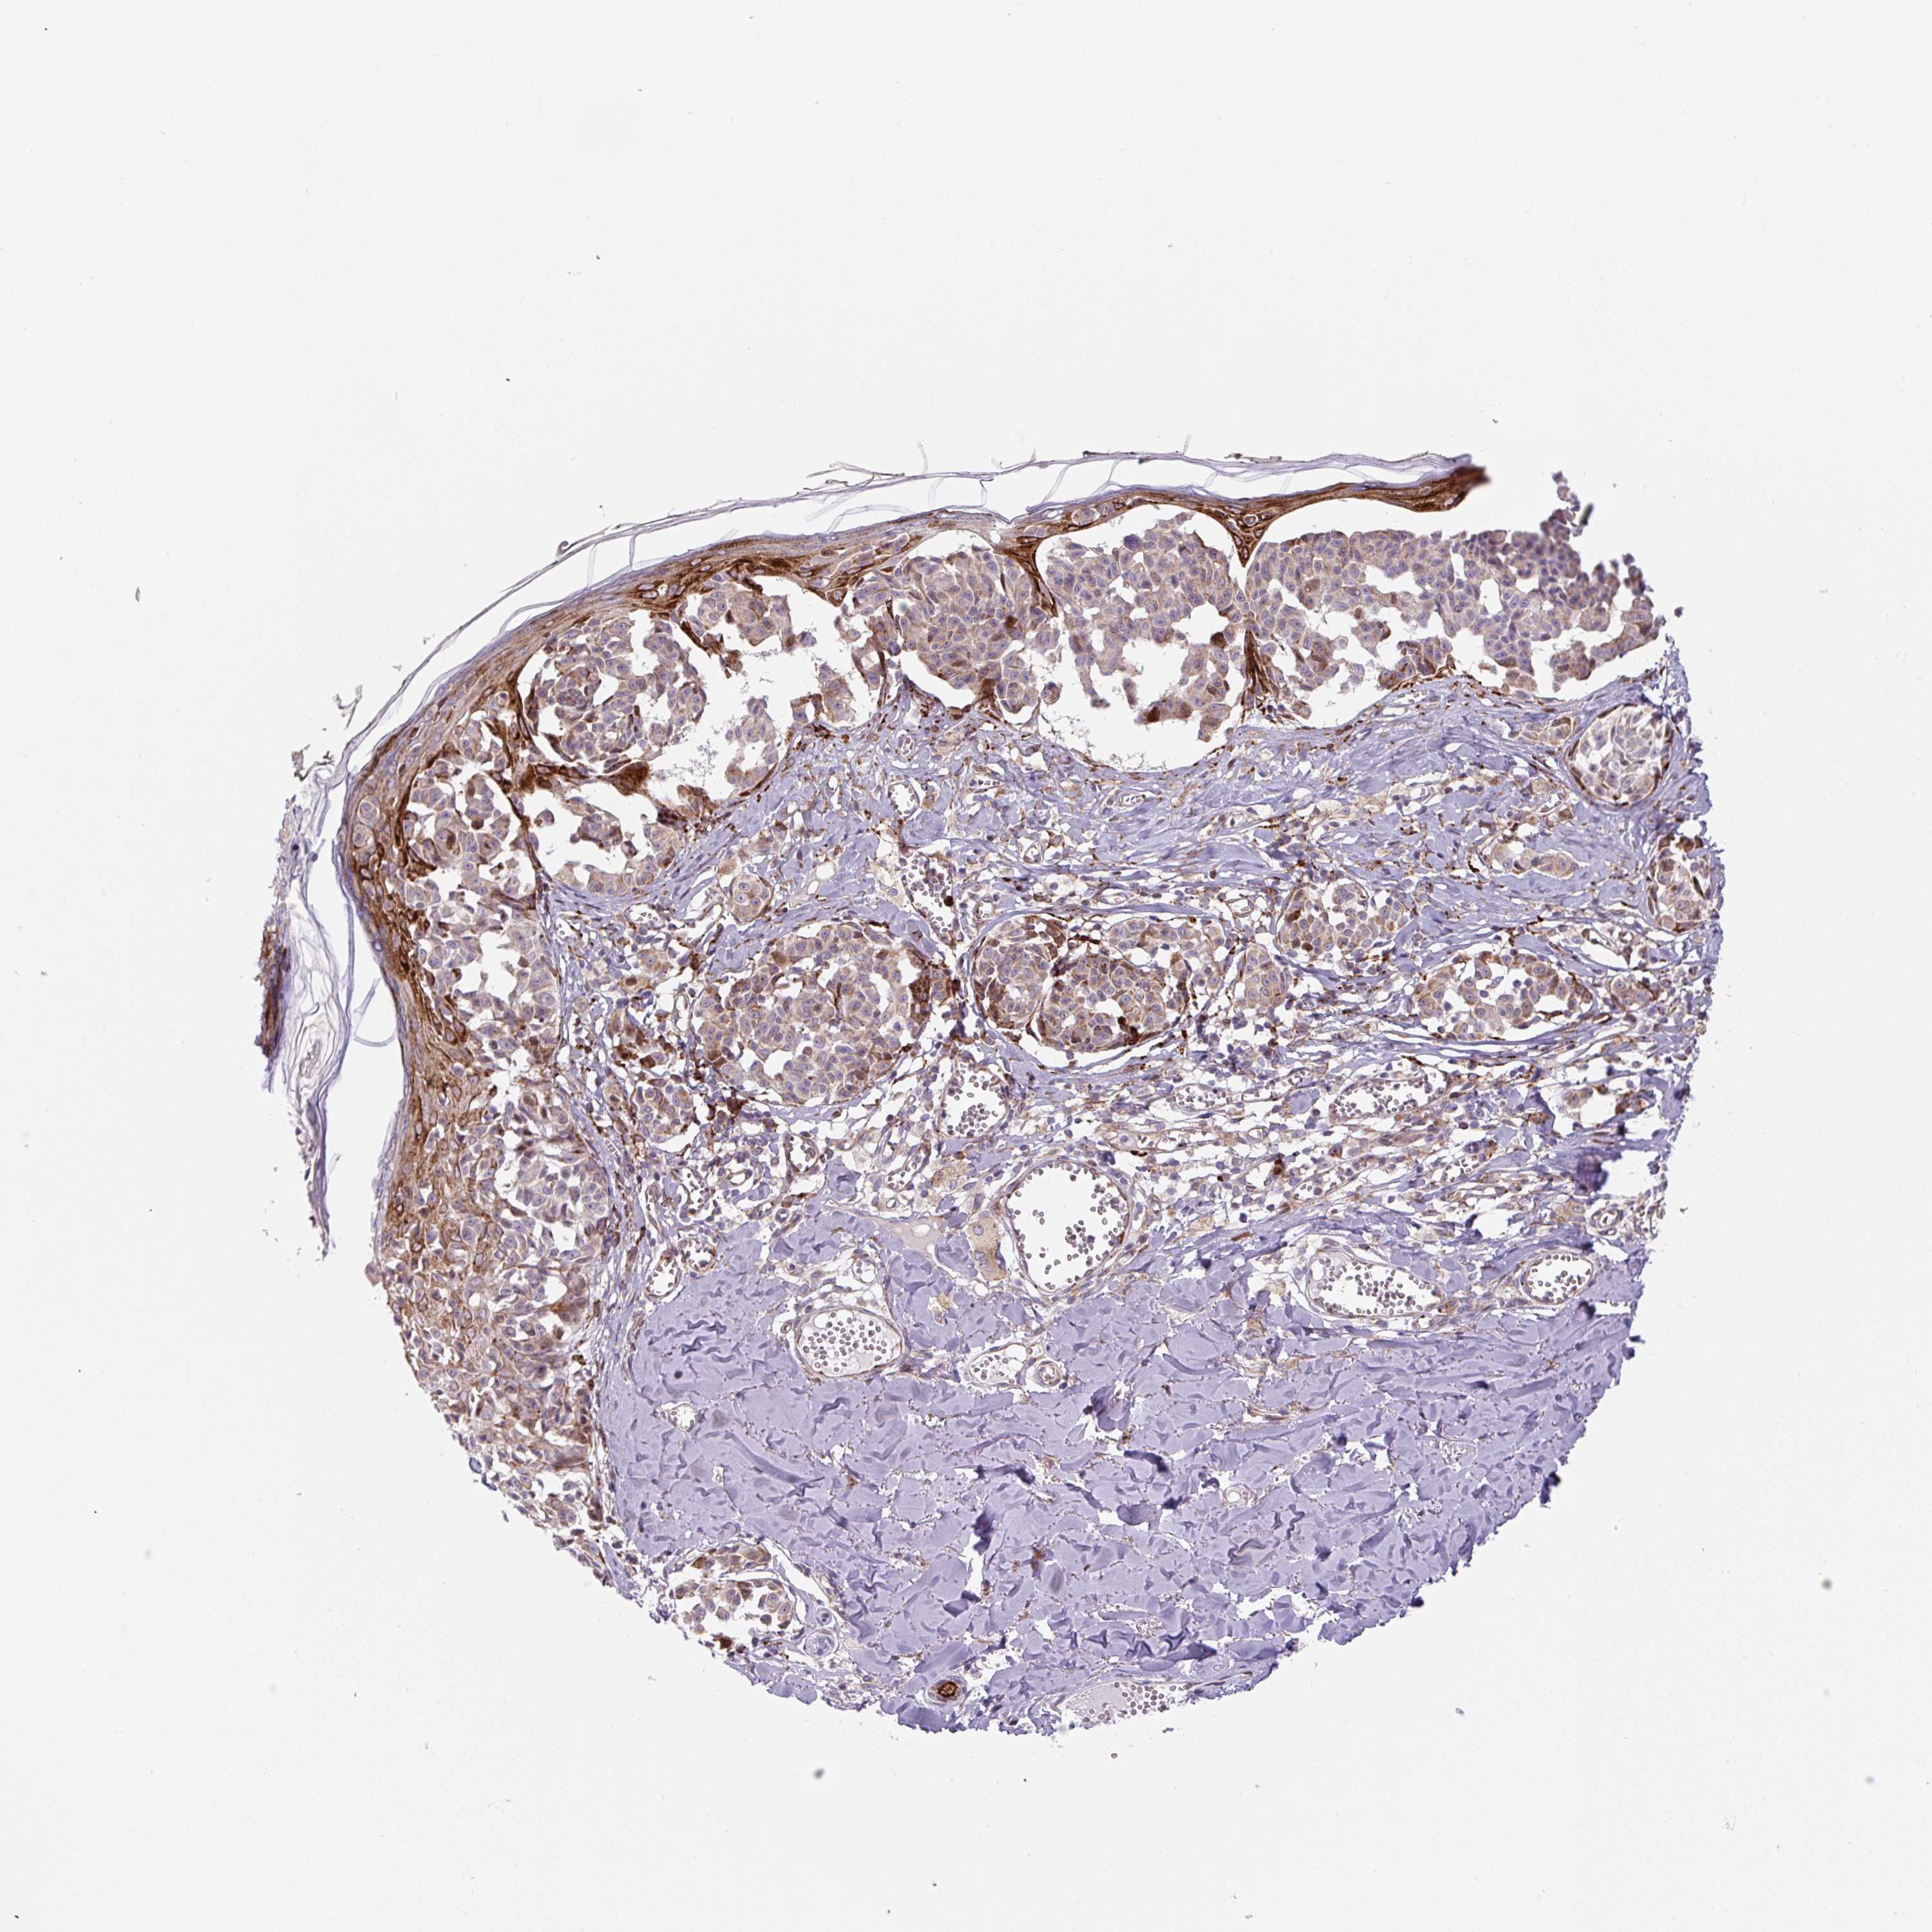

MELANOMA - Protein expressioni

A mouse-over function shows sample information and annotation data. Click on an image to view it in a full screen mode. Samples can be filtered based on level of antibody staining by selecting one or several of the following categories: high, medium, low and not detected. The assay and annotation is described here.

Note that samples used for immunohistochemistry by the Human Protein Atlas do not correspond to samples in the TCGA dataset.

Antibody stainingi

Antibody staining in the annotated cell types in the current human tissue is reported as not detected, low, medium, or high, based on conventional immunohistochemistry profiling in selected tissues. This score is based on the combination of the staining intensity and fraction of stained cells.

Each image is clickable and will lead to virtual microscopy that enables deeper exploration of all samples and also displays staining intensity scores, fraction scores and subcellular localization as well as patient and tissue information for each sample.

Antibody HPA054579

Staining

High

Medium

Low

Not detected

Intensity

Strong

Moderate

Weak

Negative

Quantity

>75%

75%-25%

<25%

None

Location

Nuclear

Cytoplasmic/membranous

Cytoplasmic/membranous,nuclear

Malignant melanoma, NOS

Malignant melanoma, Metastatic site